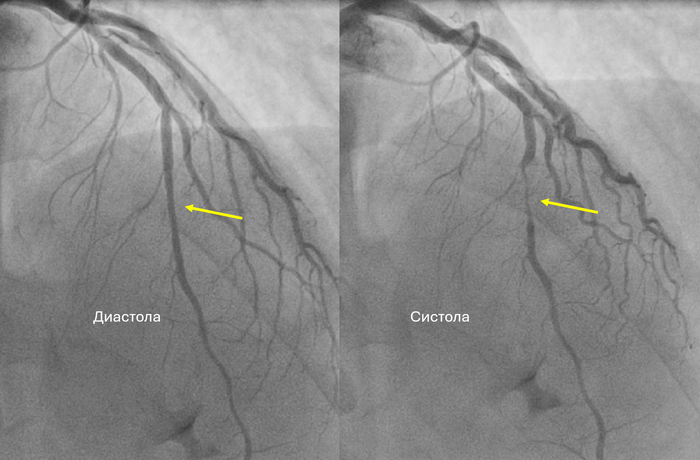

При терминальной стадии артроза голеностопного сустава (когда сустав тотально разрушен), есть два основных варианта хирургического лечения:

эндопротезирование (Эп, использую такие сокращения для простоты понимания) — ставят искусственный сустав, чтобы сохранить движение.

атродез (Ар) — сустав “выключают”: сращивают кости, движения в голеностопе больше нет, зато обычно уходит боль. Сразу обговорю: человек инвалидом не становится, он может ходить и даже заниматься спортом.

Слева артродезирование (то есть голеностопного сустава больше нет), а справа эндопротезирование (его заменили на искусственный).

То есть в этой базе повторные большие операции после эндопротеза встречались чаще. И это нормальные данные. Связано это с особенностью эндопротезирования голеностопного сустава. Так, на уровне голеностопного сустава меньше объема кости (а соответственно меньший контакт кость-имплант) и меньший объемы мышц (а они важны для стабилизации сустава). И другой важный аспект, когда у активного человека сохраняется подвижность голеностопного сустава и исчезает боль, то он (что логично) начинает давать большие нагрузки, что приводит к быстрому износу протеза голеностопного сустава.

Операции на соседних суставах заднего отдела стопы (например, подтаранный сустав):Через 25 лет артродез соседних суставов понадобился примерно:

после артродеза — 8,6%,

после эндопротеза — 6,8%. Статистически значимой разницы нет. Однако, эндопротезирование это операция, которая направлена на профилактику развития артроза в смежных суставах. Стопа так устроена, что когда мы блокируем один сустав, обязательно перегружается близлежащий другой.

Так выглядит постепенно увеличение операций по артродезированию суставов. Сначала был замкнут голеностопный сустав, затем просыпанный, а после и сустава